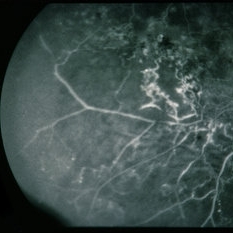

BRVO - Massive Exudate from Collaterals

Feb 24 2014 by David Callanan, MD

66-year-old female with BRVO - massive exudate from collaterals, 20/70 OD; 20/25 OS in 1985; +HTN, glaucoma; 20/200 OD 1987.

Condition/keywords: branch retinal vein occlusion (BRVO), collaterals, exudate